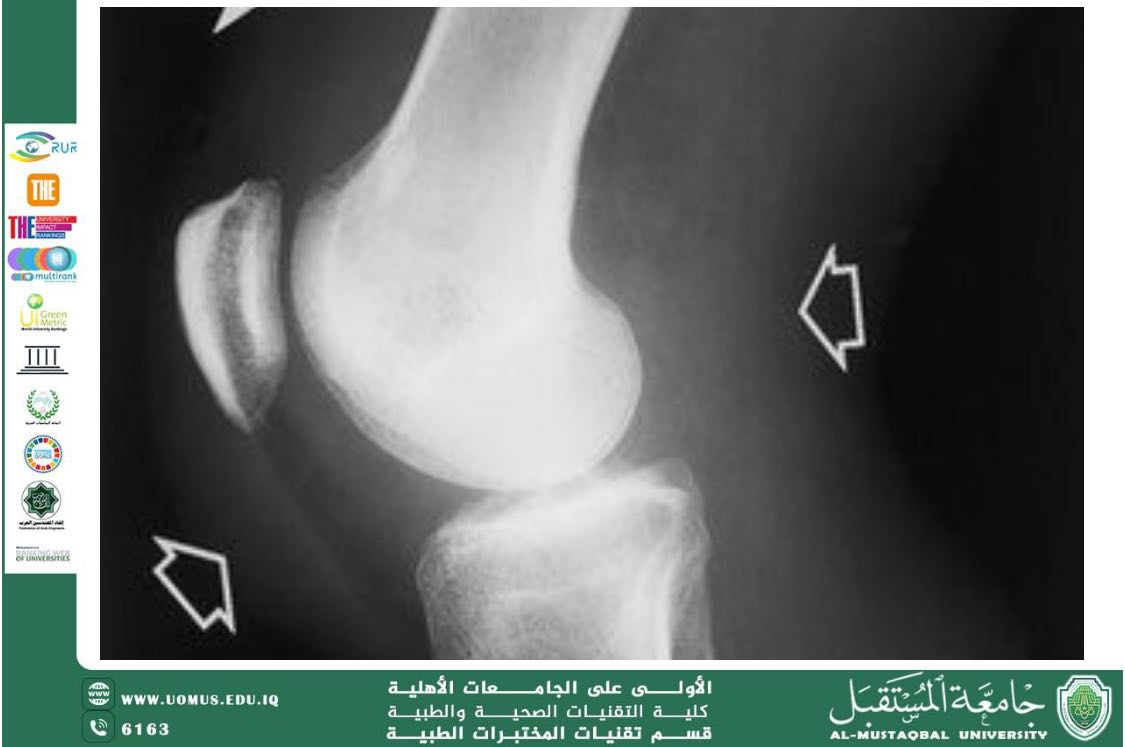

1. Introduction Bacterial joint infection, clinically known as septic arthritis, is a serious medical condition that occurs when bacteria enter a joint, leading to inflammation, pain, and potential joint destruction. Early diagnosis and treatment are essential to prevent permanent damage and systemic complications. 2. Epidemiology Septic arthritis affects all age groups, but it is more common in: • Older adults • Individuals with weakened immune systems • Patients with pre-existing joint diseases (e.g., rheumatoid arthritis) • People with prosthetic joints The incidence ranges from 2 to 10 cases per 100,000 people annually in developed countries, with higher rates in certain high-risk populations. 3. Pathogenesis – How Bacteria Infect Joints Bacteria can reach the joint through several routes: 1. Hematogenous spread: Bacteria travel through the bloodstream from another site in the body (e.g., skin or urinary tract) and settle in the synovial membrane. 2. Direct inoculation: Through trauma, surgery, injections, or penetrating injuries. 3. Contiguous spread: From nearby infected tissues, such as osteomyelitis. Once bacteria invade the joint: • Synovial inflammation occurs. • White blood cells, especially neutrophils, enter the joint and release enzymes and cytokines. • These enzymes can rapidly damage cartilage and bone. 4. Common Causative Organisms • Staphylococcus aureus: most common overall • Streptococcus species: common in children and adults • Neisseria gonorrhoeae: in sexually active adults • Gram-negative bacilli: in older adults and immunocompromised patients • Rare pathogens: after surgery or in patients with prosthetic joints 5. Clinical Presentation Patients typically present with: • Sudden onset joint pain • Swelling and warmth • Limited range of motion • Fever and general malaise Large joints such as the knee, hip, shoulder, and ankle are often affected. 6. Diagnosis 6.1 Physical Examination • Tenderness over the joint • Redness • Pain on movement 6.2 Laboratory Tests • Elevated white blood cell count • Increased inflammatory markers (CRP, ESR) 6.3 Synovial Fluid Analysis Joint aspiration is the gold standard for diagnosis: • Appearance: cloudy and purulent • White blood cell count: typically >50,000 cells/mm³ • Gram stain and culture identify the causative bacteria 6.4 Imaging • X-rays: may show joint space changes • Ultrasound or MRI: useful for early detection 7. Treatment Treatment usually includes: 7.1 Antibiotic Therapy • Initial empiric broad-spectrum antibiotics • Adjusted according to culture results • Typical duration: 2–6 weeks 7.2 Joint Drainage • Needle aspiration • Repeated aspiration or surgical washout, especially in large joints 7.3 Supportive Care • Pain management • Physical therapy to maintain joint function after infection control 8. Complications If treatment is delayed or absent: • Joint destruction • Osteomyelitis • Sepsis • Chronic pain and reduced mobility 9. Prevention • Prompt treatment of bacteremia and skin infections • Use of sterile techniques during joint procedures • Vaccination for at-risk individuals (e.g., pneumococcal vaccine) 10. Conclusion Bacterial joint infection is a medical emergency. Early recognition, accurate diagnosis, and aggressive treatment are essential to preserve joint integrity and prevent life-threatening complications. Al-Mustaqbal University is the first university in Iraq Department of Medical Laboratory Techniques – First in the Iraqi National Ranking.